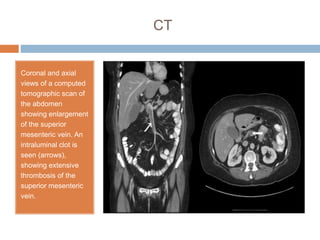

CT

Coronal and axial

views of a computed

tomographic scan of

the abdomen

showing enlargement

of the superior

mesenteric vein. An

intraluminal clot is

seen (arrows),

showing extensive

thrombosis of the

superior mesenteric

vein.

CT Coronal and axial viewsof a computed tomographic scan of the abdomen showing enlargement of the superior mesenteric vein. An intraluminal clot is seen (arrows), showing extensive thrombosis of the superior mesenteric vein.